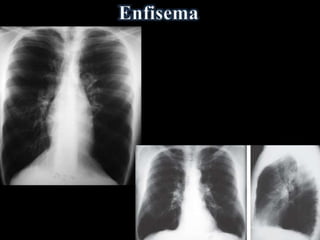

• Rebaixamento diafragmático(Costela: 11a ou 12a posterior; 7a anterior) • Retificação da cúpula • Coração alongado e verticalizado (em gota), diâmetro transverso < 11,5 cm • Aumento do tórax no diâmetro AP (em barril) • Aumento do espaço claro retroesternal (>2,5cm) • Aumento da Transparência Pulmonar ENFISEMA: • Bolhas - Área de maior radiotransparência >1cm, avascular, podendo estar delimitada por fina linha branca - Coalescência de alvéolos rotos • Atenuação da trama vascular periférica e proeminência dos vasos hílares